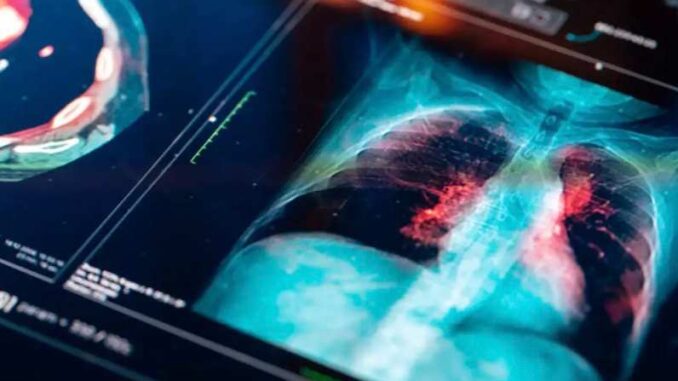

Prueban la primera vacuna contra el cáncer de pulmón, ¿cómo funciona?

Un paciente británico recibió la primera vacuna contra el cáncer de pulmón, la nueva inmunoterapia contra el cáncer más letal del mundo.